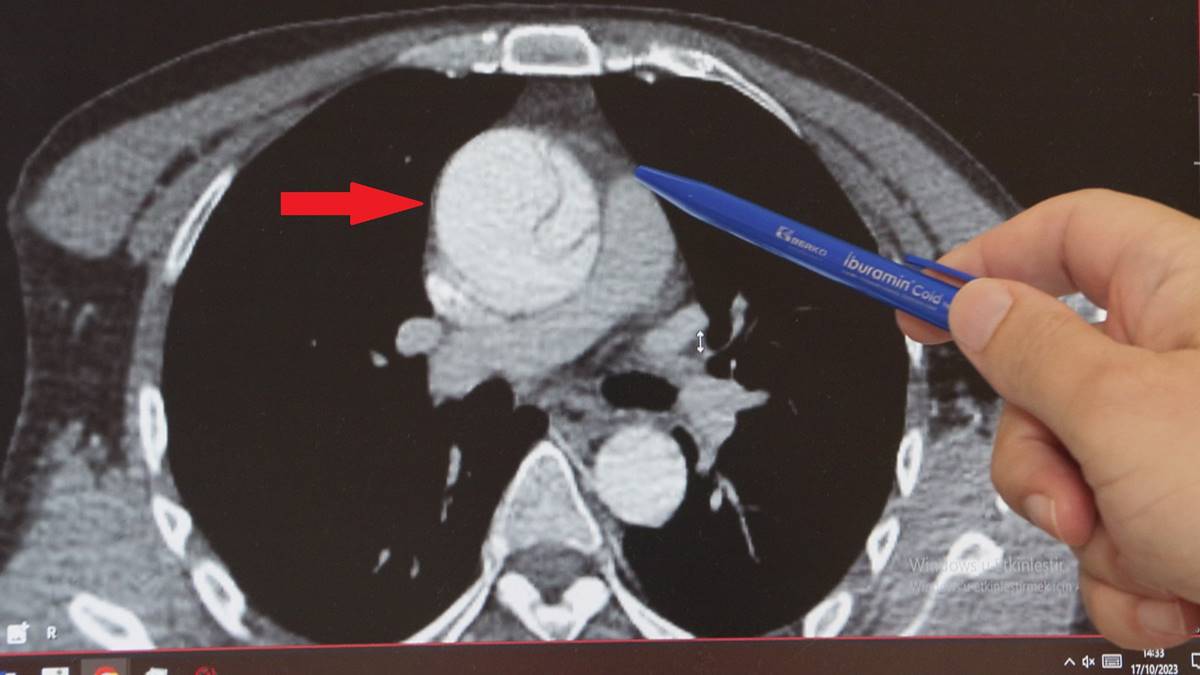

Normalde 2 santim çapında olması gereken aort damarı anevrizma (balonlaşma) nedeniyle genişleyerek neredeyse 3 katına ulaşmış, damar duvarında yırtığa neden olmuştu. Hayati riski olduğu anlaşılan Mustafa Turan, kalp damar cerrahisi ekibi tarafından acilen ameliyata alındı.

"Arkadaşlarıyla konuşurken böyle bir boğazında düğümlenme şikayeti oluyor. Bunun üzerine ambulansla acile geliyor. Tetkikleri yapılıyor, daha çok mide şikayetleri düşünülerek o yönde tetkikler yapılıyor ve tedavisi verilip gönderiliyor. Ağrıları geçmeyince tekrar acile geliyor, acildeki doktor arkadaşlarımızın dikkati ve özeni sayesinde ayrıntılı tetkik yapılıyor ve bu sırada aort diseksiyonu olduğu görülüyor. Bize konsülte edildi ve hızlı bir şekilde ameliyathanemizi ayarladık, acilen ameliyata aldık."

Aort anevrizmasının çoğunlukla sessiz ilerlediğini kaydeden Prof. Dr. Ebuzer Aydın, genellikle başka tetkikler yapılırken tesadüfen teşhis edilen hastalıkta en önemli şeyin, aort damarında yırtık meydana geldikten sonra kaybedilen her 1 saat için ölüm riskinin yüzde 1 artması olduğunu vurguladı ve şu bilgileri paylaştı:

"Acil ameliyatla, elektif (planlı) ameliyat arasında ölüm riski açısından, ameliyattaki diğer riskler ve hastaya getirdiği başka tehlikeler açısından çok ciddi farklar var. Her 1 saat için ölüm riski yüzde 1 artar. Bu hastalar çoğunlukla kanama ve getirdiği bir takım diğer komplikasyonlarla kaybedilir. Planlı ameliyatlarda ölüm riski yaklaşık yüzde 5 iken diseksiyon meydana geldiğinde bu risk yüzde 20-25'lere kadar çıkabiliyor. Yani planlı bir anevrizma ameliyatı ile diseksiyon ameliyatı arasında 4-5 kat fark var."